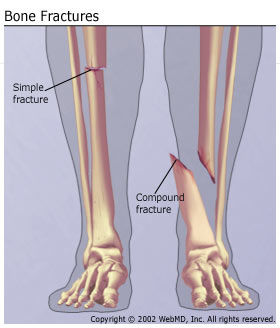

2. Fractures

1. Simple

1. is when the bone is not completely cracked through

2. Commnuted

1. is when the bone is shattered

2. Compound

1. is like simple, except the bone is cracked through??